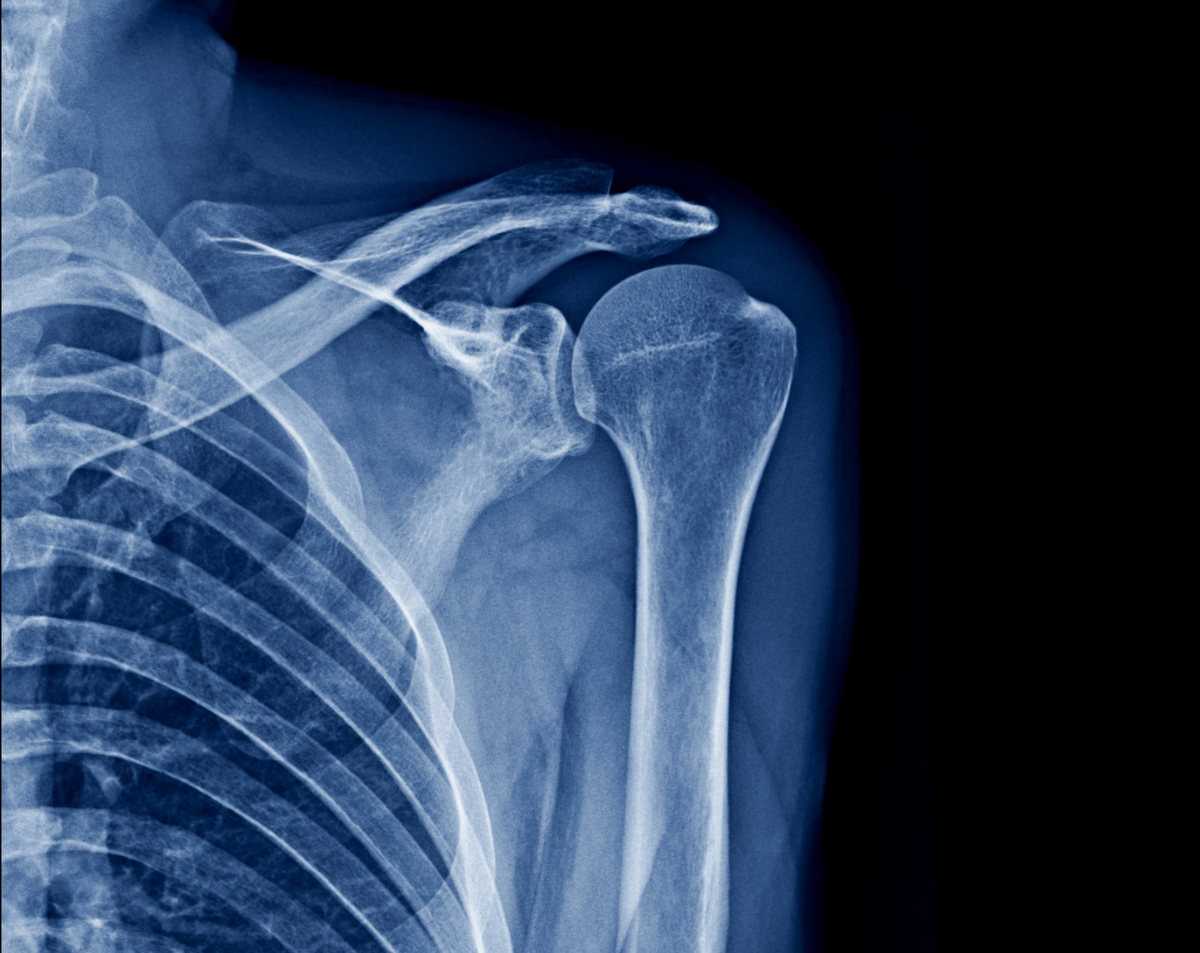

A shoulder X-ray provides clear images of the bones and joints that make up the shoulder, including the clavicle, scapula, and upper arm. Physicians often order this study after an injury or to evaluate chronic pain, arthritis, or suspected joint damage. At Desert Mobile Medical, we bring advanced diagnostic technology directly to you. With our mobile X-ray service, you receive accurate results in the comfort of your home, office, or care facility—without waiting rooms or long commutes.

Doctors rely on shoulder X-rays to evaluate:

Injuries & Fractures – After falls, sports accidents, or sudden trauma.

Chronic Shoulder Pain – To identify arthritis, bone spurs, or degenerative changes.

Dislocations – To confirm alignment after the shoulder has shifted out of place.

Post-Surgical Monitoring – To ensure proper healing and hardware placement.

Limited Mobility or Weakness – To investigate bone-related causes of movement issues.

Because it’s quick, accurate, and noninvasive, a shoulder X-ray is often the first diagnostic step before advanced imaging like MRI or CT.